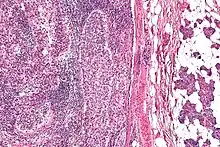

| Micrograph of a sebaceous carcinoma (left of image) metastatic to the parotid gland (right of image). H&E stain. | |